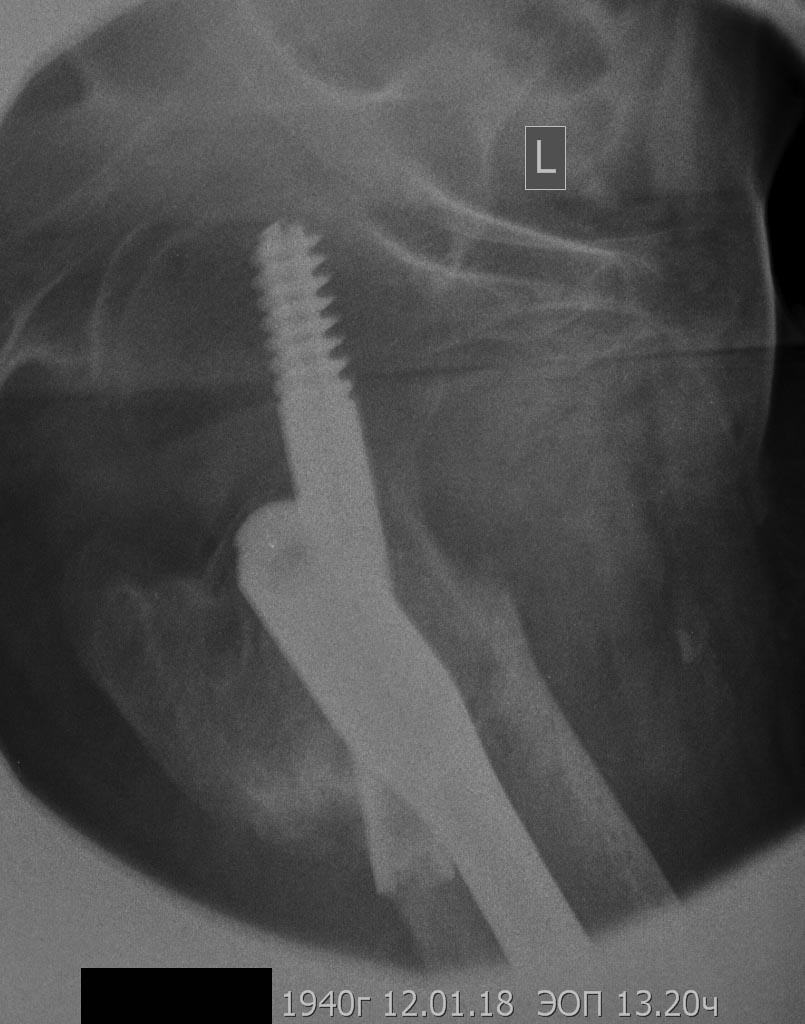

добрый день! вроде все получилось сделать,закрыто,чрезкожная остеотомия. дистальная пластина тоже малоинвазивно

мыщелки

Спесибо) на столе попробовали растянуть но безуспешно.винт 6мм от стержневого аппарата.после остеотомии диафиз стремился кнутри пришлось тклоняющую спицу провести спереди назад.